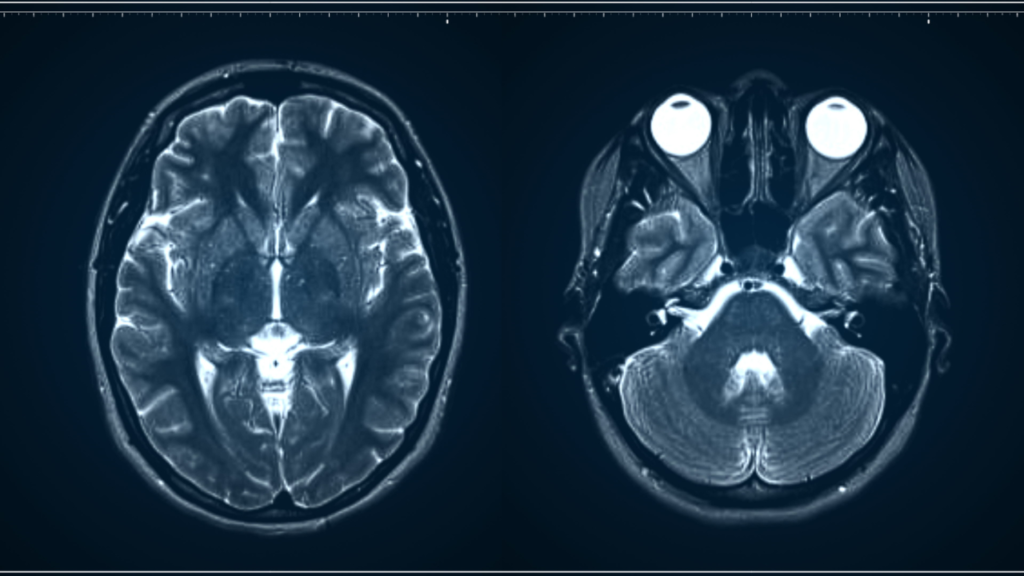

Accurate neuro-imaging interpretation is central to stroke care, trauma assessment, headache evaluation, seizure workups, and diagnosis of degenerative or infectious conditions. RadWorks provides subspecialist neuroradiology reads that focus on clinically relevant findings, timely reporting, and clear guidance for physicians managing acute and chronic neurological disorders.

Yes. This includes MRI with diffusion, perfusion, spectroscopy, and CT/MR angiography for vascular evaluation.